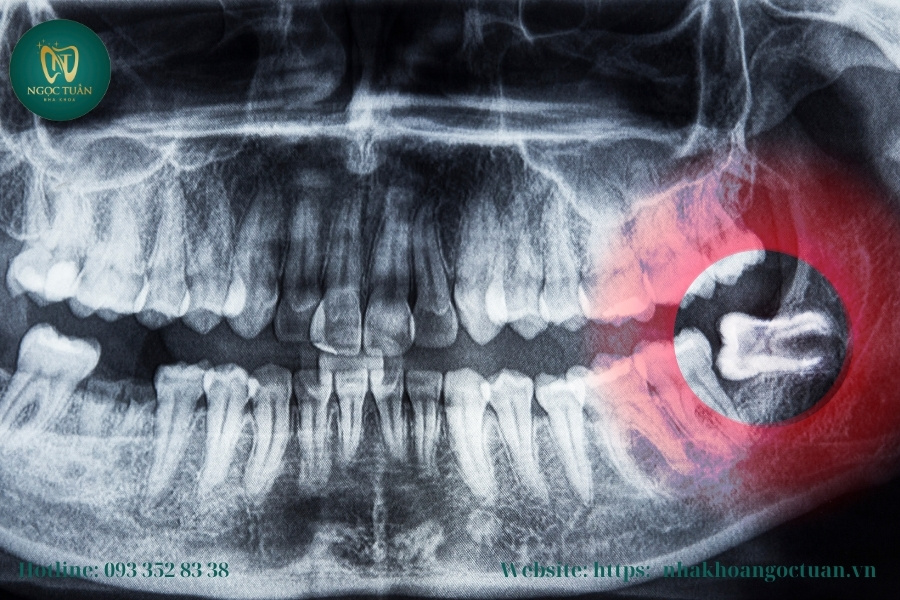

Răng Khôn Mọc Lệch Và Chèn Ép Các Răng Lân Cận

Khi răng khôn không mọc đúng vị trí, chúng thường bị lệch về phía ngoài hoặc trong, gây ra hiện tượng chèn ép các răng lân cận. Sự chèn ép này không chỉ làm thay đổi vị trí của răng mà còn ảnh hưởng đến cấu trúc hàm, gây ra sự mất cân đối trong răng miệng. Các răng bị chèn ép có thể di chuyển, tạo ra khoảng cách không đều, làm cho hàm răng trở nên khó chịu và ảnh hưởng đến khả năng cắn nhai. Sự mọc lệch của răng khôn cũng có thể dẫn đến các vấn đề về hàm, như đau nhức và khó khăn trong việc bảo vệ sức khỏe răng miệng tổng thể.

Nguy Cơ Sâu Răng, Viêm Nướu Và Nhiễm Trùng

Khi răng khôn mọc không đúng vị trí, chúng dễ tạo thành các kẽ hở, nơi thức ăn và vi khuẩn có thể mắc kẹt. Việc này dẫn đến sự tích tụ của mảng bám, làm tăng nguy cơ phát triển sâu răng và viêm nướu. Nếu không được xử lý kịp thời, vi khuẩn trong mảng bám có thể xâm nhập vào mô răng, gây nhiễm trùng, làm cho răng trở nên yếu hơn và dễ rơi ra. Các vấn đề này không chỉ gây đau đớn mà còn có thể lan rộng, ảnh hưởng đến các răng khác và thậm chí cả sức khỏe tổng thể.